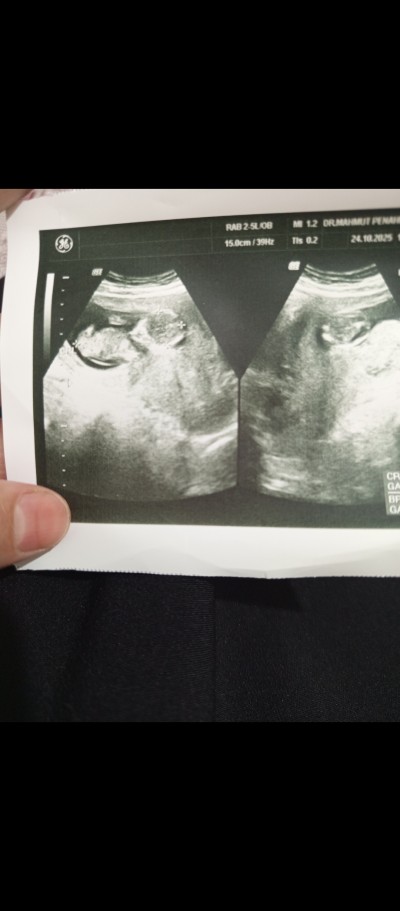

13+3 haftalık ama ultrason da 14 haftalık.

Gebelik haftası 13+3 haftalık